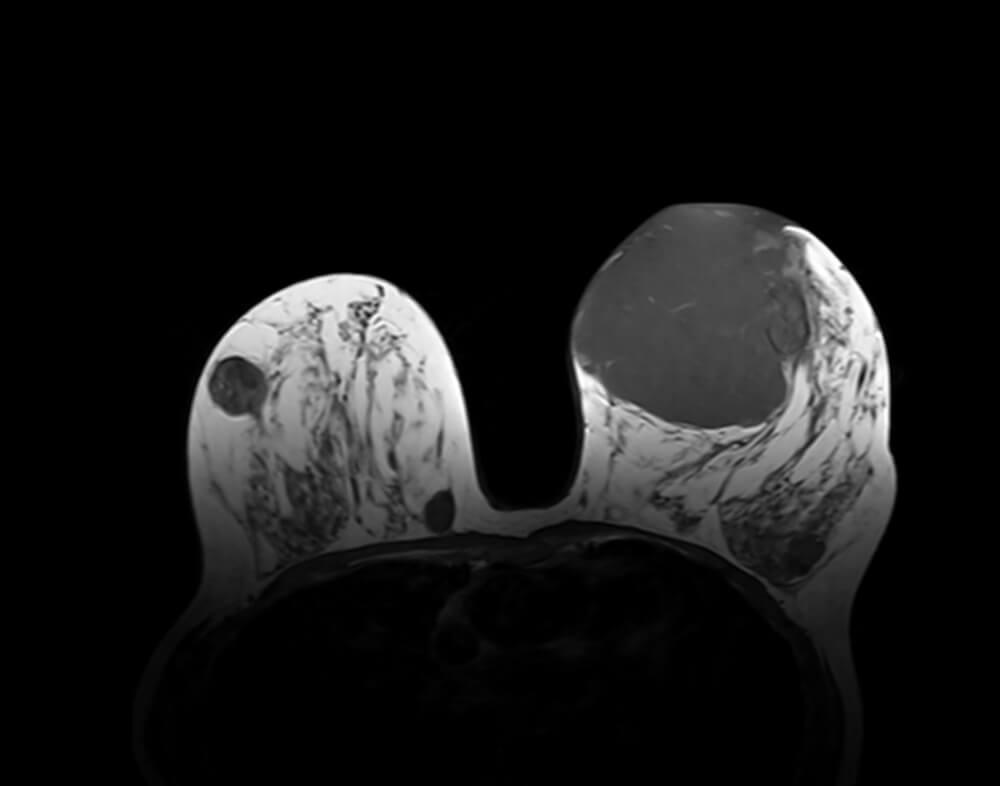

Καλοήθης Φυλλοειδής Όγκος

Η κλινική εικόνα και τα απεικονιστικά ευρήματα, ειδικά σε μικρότερους φυλλοειδείς όγκους, είναι παρόμοια με του ιναδενώματος.

Σε μεγάλους φυλλοειδείς όγκους μπορεί να υπάρχουν χαρακτηριστικά ευρήματα στο υπερηχογράφημα.